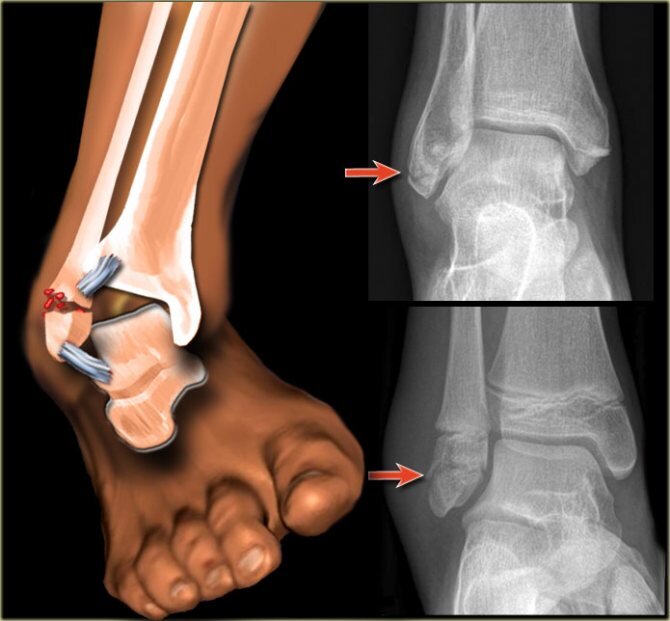

Первичный диагноз ставят, основываясь на данных внешнего осмотра. Врач изучает обстоятельства случившегося, исследует механизм полученной травмы. Окончательный диагноз может быть поставлен травматологом только по результату изучения рентгеновских снимков.

Достаточно часто вместе с переломом диагностируется разрыв голеностопных суставных связок и разрыв капсулы голеностопа. Сложным считается одновременный перелом лодыжки и вывих голеностопного сустава.